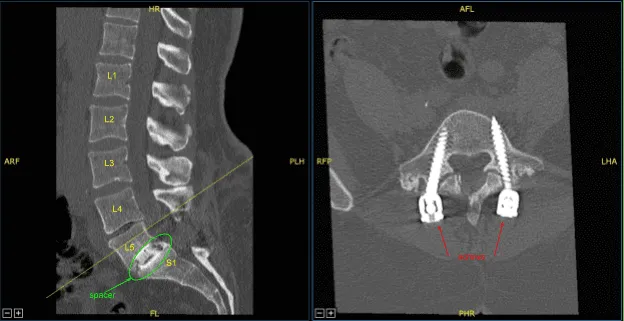

Locking caps at L5 and S1 were removed. The rods were removed. The screws were checked and were found to be tight and therefore were left in place. Next, the fixed neuronavigation arrays for the right posterior-superior iliac crest with two Schanz pins. Sterilely draped the patient to obtain the CT scan.

Demineralized bone matrix allograft was placed into the interspace and then titanium expandable interbody device was placed under fluoroscopic guidance after sterilely draping the C-arm unit. AP and lateral imaging showed correct positioning and then the cage was expanded to the proper fit and the subsequent x-ray showed good positioning both in the midline and anteroposterior.

Next, a new CT scan was obtained, which showed correct positioning of the new pedicle screws and interbody spacer. Bilateral transverse processes of L4, L5, and lateral ala were decorticated for arthrodesis. Pre-cut, pre-contoured rods reflected and placed across the tulips from L4 to S1 and secured with locking caps and finally tightened with the torque and anti-torque device.